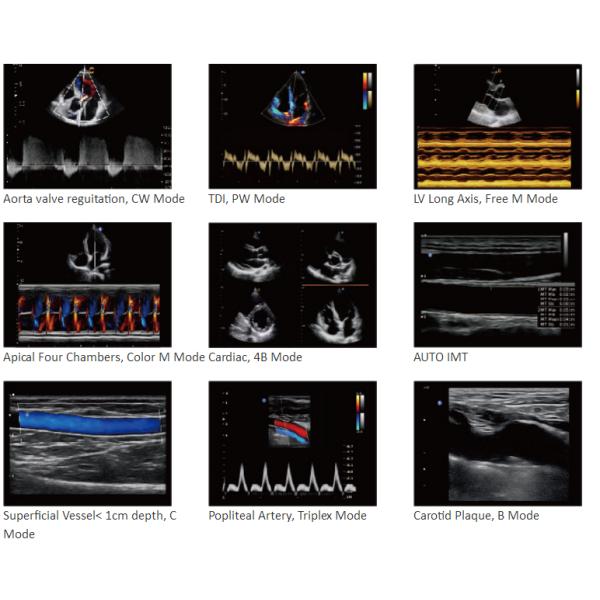

Advanced Cardiac Package: CW ,TDI ,Semi-Automatic Trace ,Tei Index ,PISA.

Wide Clinic Applications: Cardiology,OB&GYN, Radiology ,Abdominal, Pediatric,MSK,Breast,Vascular and Small parts etc.

Clinic value and applications

Mobility Innovative Highlight Portable Ultrasound Scanner With 15 Inch LED Display Images |